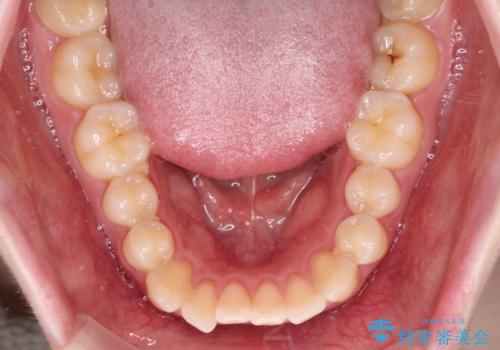

強い舌の突出癖により、上下前歯が前方に飛び出しており、特に上顎前歯は下顎よりも更に前方に位置している状態でした。

上顎前歯をしっかりと後方に移動させるため、口蓋側にアンカースクリューと補助装置を併用し、上下左右の第一小臼歯4本を抜歯し、ワイヤー装置にて矯正治療を行うこととしました。